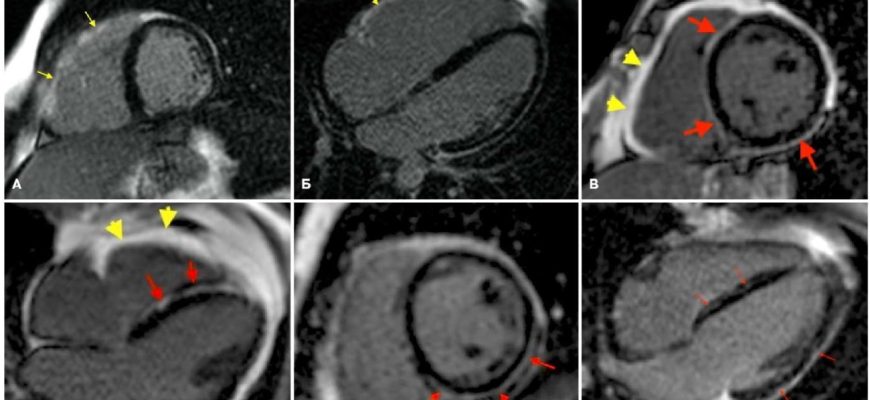

Искусственный Интеллект на Страже Здоровья: Наш Опыт Разработки ИИ для Анализа МРТ В современном мире, где объемы медицинских данных растут экспоненциально

ИИ в трансплантологии: Новая надежда или технологическая утопия? Приветствую вас‚ дорогие читатели! Сегодня мы погрузимся в захватывающую и одновременно